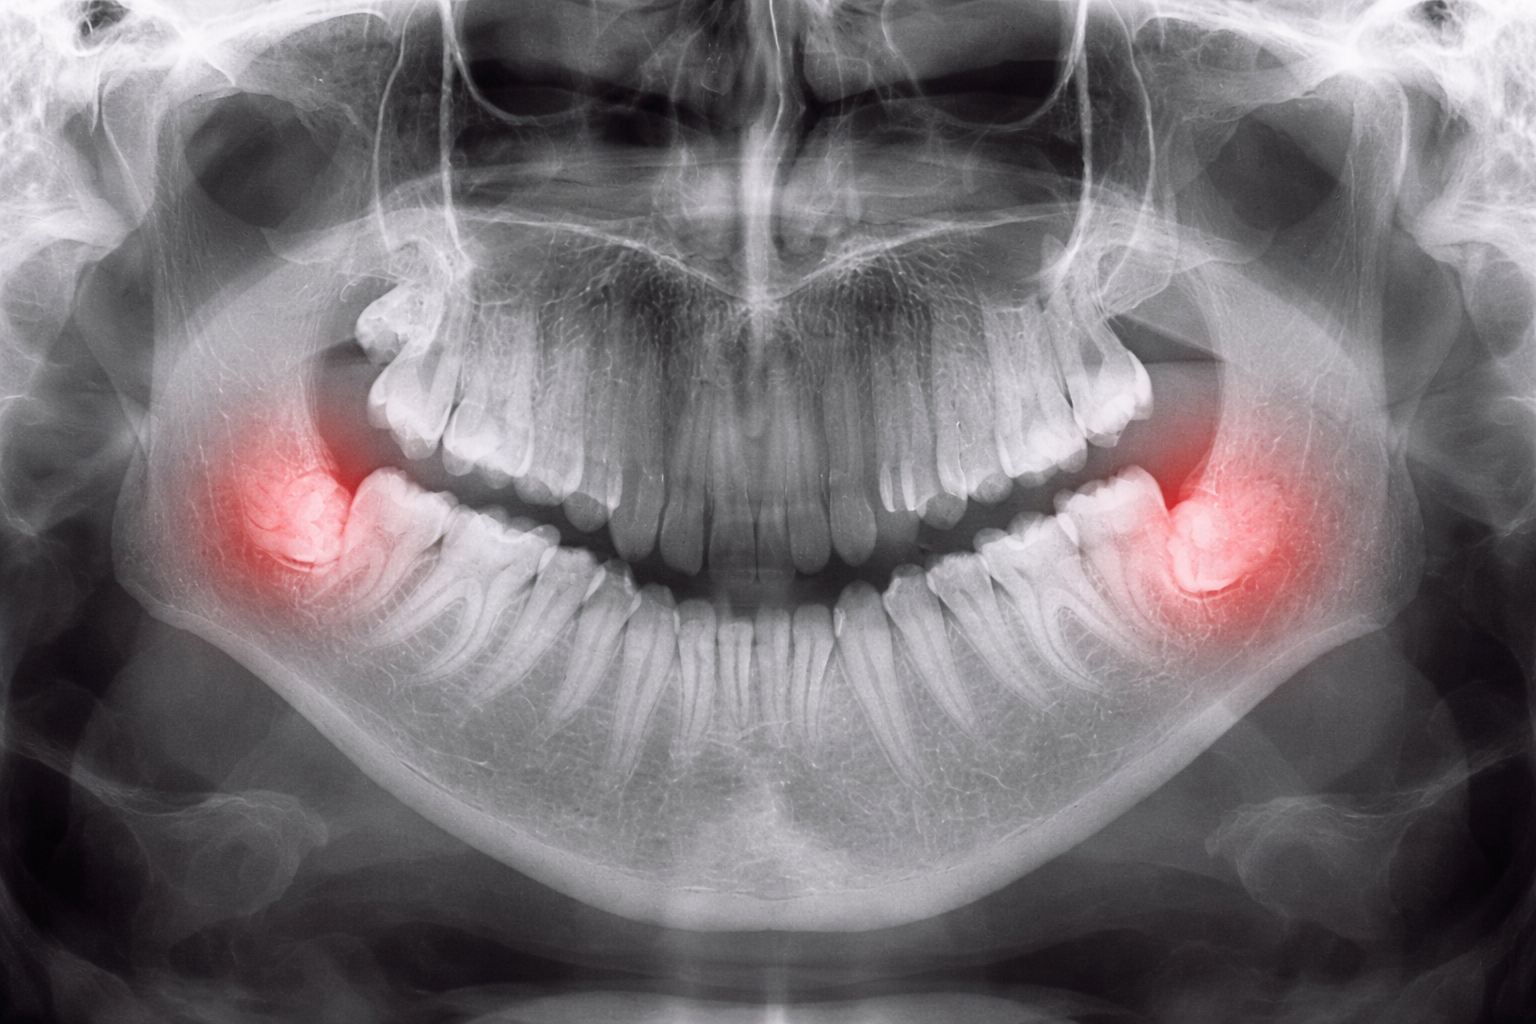

Зубы мудрости — это восьмые зубы, которые прорезываются обычно в возрасте 17–25 лет.

- растут неправильно

- остаются частично или полностью в кости

- травмируют соседние зубы и десну

Неправильное положение

Зуб растет под углом или упирается в соседний зуб — это может привести к разрушению.